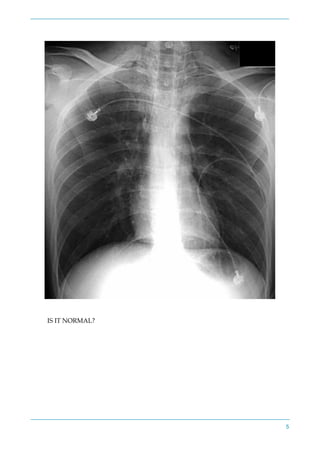

LUCKILY THE CXR FILM HAS ARRIVED

4

IS IT NORMAL?

5